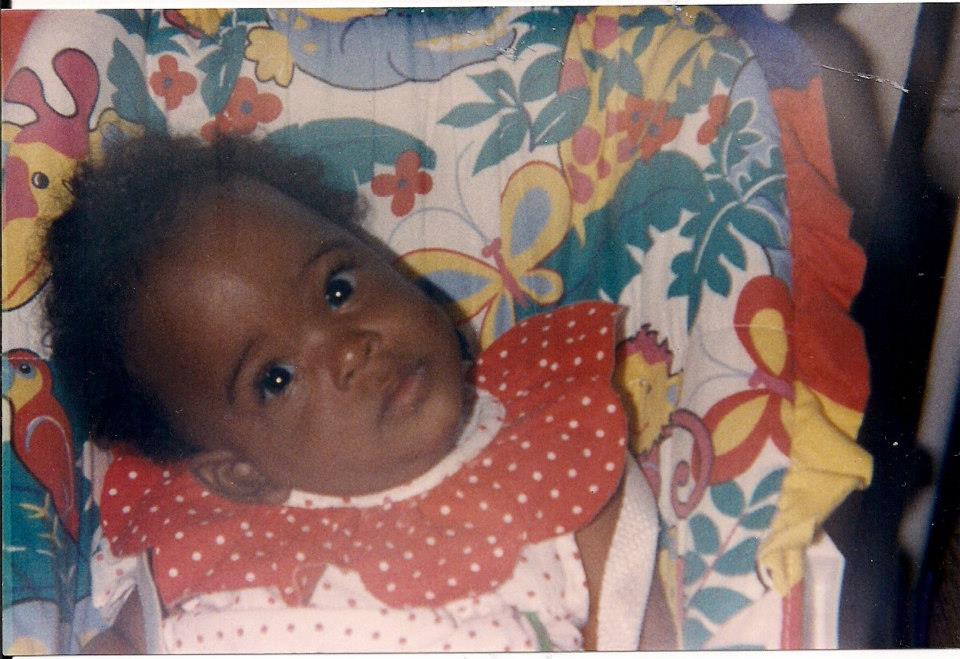

At 9 months, my parents began realizing I was not reaching development milestones in comparison to my older siblings and my mom took me to the doctor. They addressed my mom’s concerns, informed her that I had a disability, and recommended I needed to attend early intervention. I was diagnosed with Cerebral Palsy, which my parents had no idea what it was.